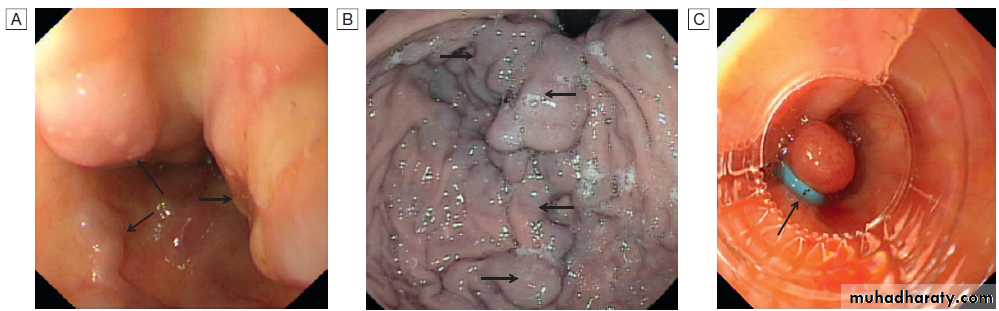

Varices: endoscopic views. A Oesophageal varices (arrows) at the lower end of the oesophagus. B Gastric varices (arrows). C Appearance of oesophageal varices following application of strangulating bands (band ligation, arrow).

and portal hypertension .The most important consequence of portal hypertension is variceal bleeding, which commonly arises from oesophageal varices located within 3–5 cm of the gastrooesophageal junction, or from gastric varices. The size of the varices, endoscopic variceal features such as red spots and stripes, high portal pressure and liver failure are all general factors that predispose to bleeding. Drugs capable of causing mucosal erosion, such as salicylates and NSAIDs, can also precipitate bleeding.